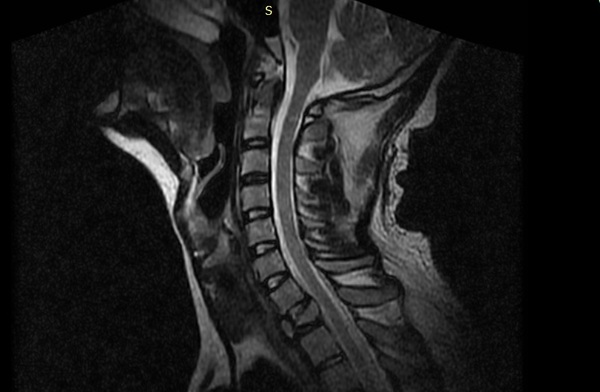

Недавно решил сделать МРТ, поскольку беспокоили боли в шее. Как оказалось это всего лишь остеохондроз, но интересней другое - на снимке обнаружилось, что я год проходил со сломанным позвонком и ничего не подозревал про это. Детали того происшествия описаны в посте выше.

Самое интересное, что пролежав в постели 3 дня после травмы я преспокойно вышел на работу и до сих пор не подозревал о серьезности случившегося и преспокойно носил тяжелые предметы, делал резкие движения и даже разок подрался.

Врач сказал, что сейчас мне ничего не угрожает, что благодаря хорошему мышечному корсету позвонок остался в куче и уже, если можно так сказать, сросся.

P.S. Хотелось бы заглянуть в глаза тому врачу, который диагностировал мне ушиб, а также заставлял ходить по корпусу поликлиники своим ходом и лазать на стол в рентген кабинете